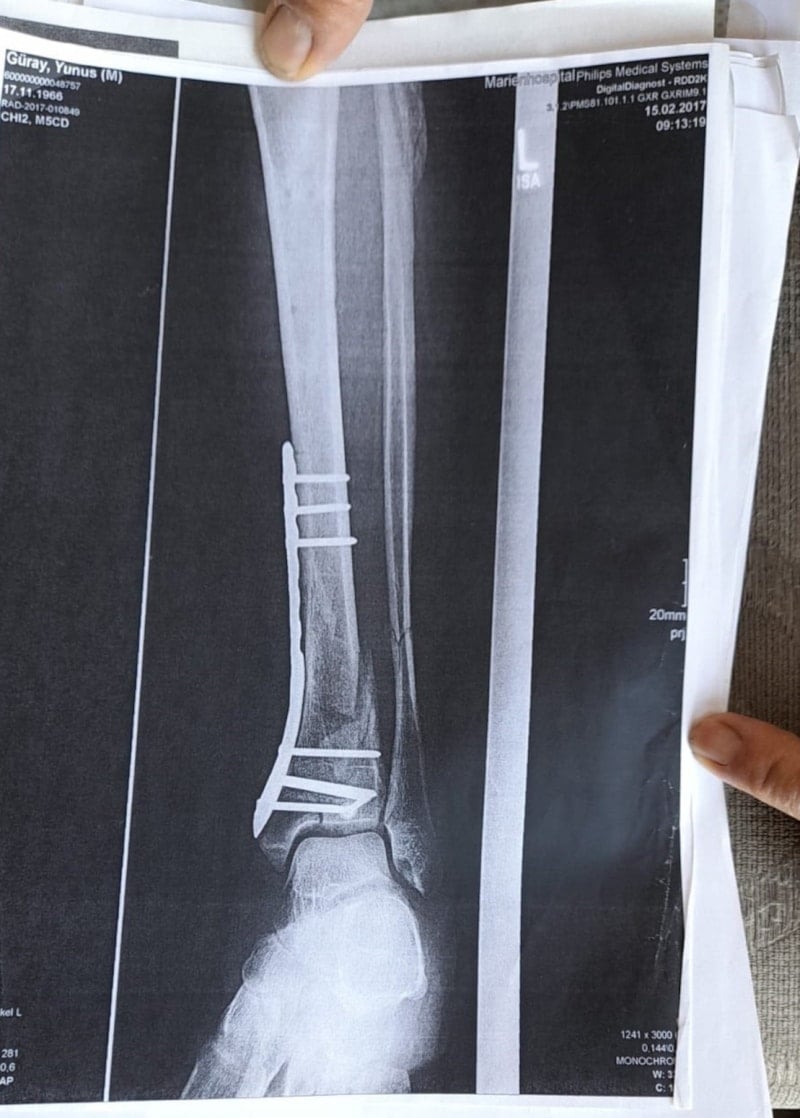

Olay yeriyle ilgili fotoğraf ve görüntüleri mahkemeye sunduklarını kaydeden Güray, "Ömrümü yediler, demir var ayağımda, sakat bıraktılar. Ayağı keseceklerdi neredeyse. Şu an kalıcı sakatlık var. 1 sene kendime gelemedim, 2 haftada bir ameliyata giriyordum. Almanya'da 3 ay hastanede kaldım ve ayağımda yüzde 3'lük engel oluştu" diye konuştu.